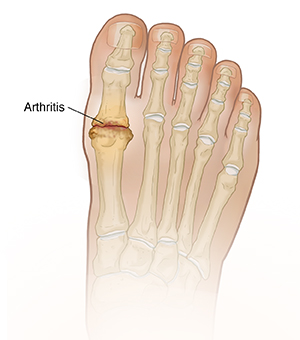

What Is Arthritis in the Foot?

Degenerative arthritis is a condition that slowly wears away joints. These are the areas where bones meet and move. At first, you may notice that the affected joint seems stiff. It may even ache. As the joint lining (cartilage) breaks down, the bones rub against each other, causing pain and swelling. Over time, small pieces of rough or splintered bone (bone spurs) develop, and the joint’s range of motion becomes limited. But movement doesn’t have to cause pain. In most cases, the pain from arthritis can be eased with medical care. If needed, surgery may be done.

The big-toe joint

When arthritis affects your big toe, your foot hurts when it pushes off the ground. Arthritis often appears in the big-toe joint along with a bony bump at the side of the joint (bunion) or a bone spur on top of the joint.